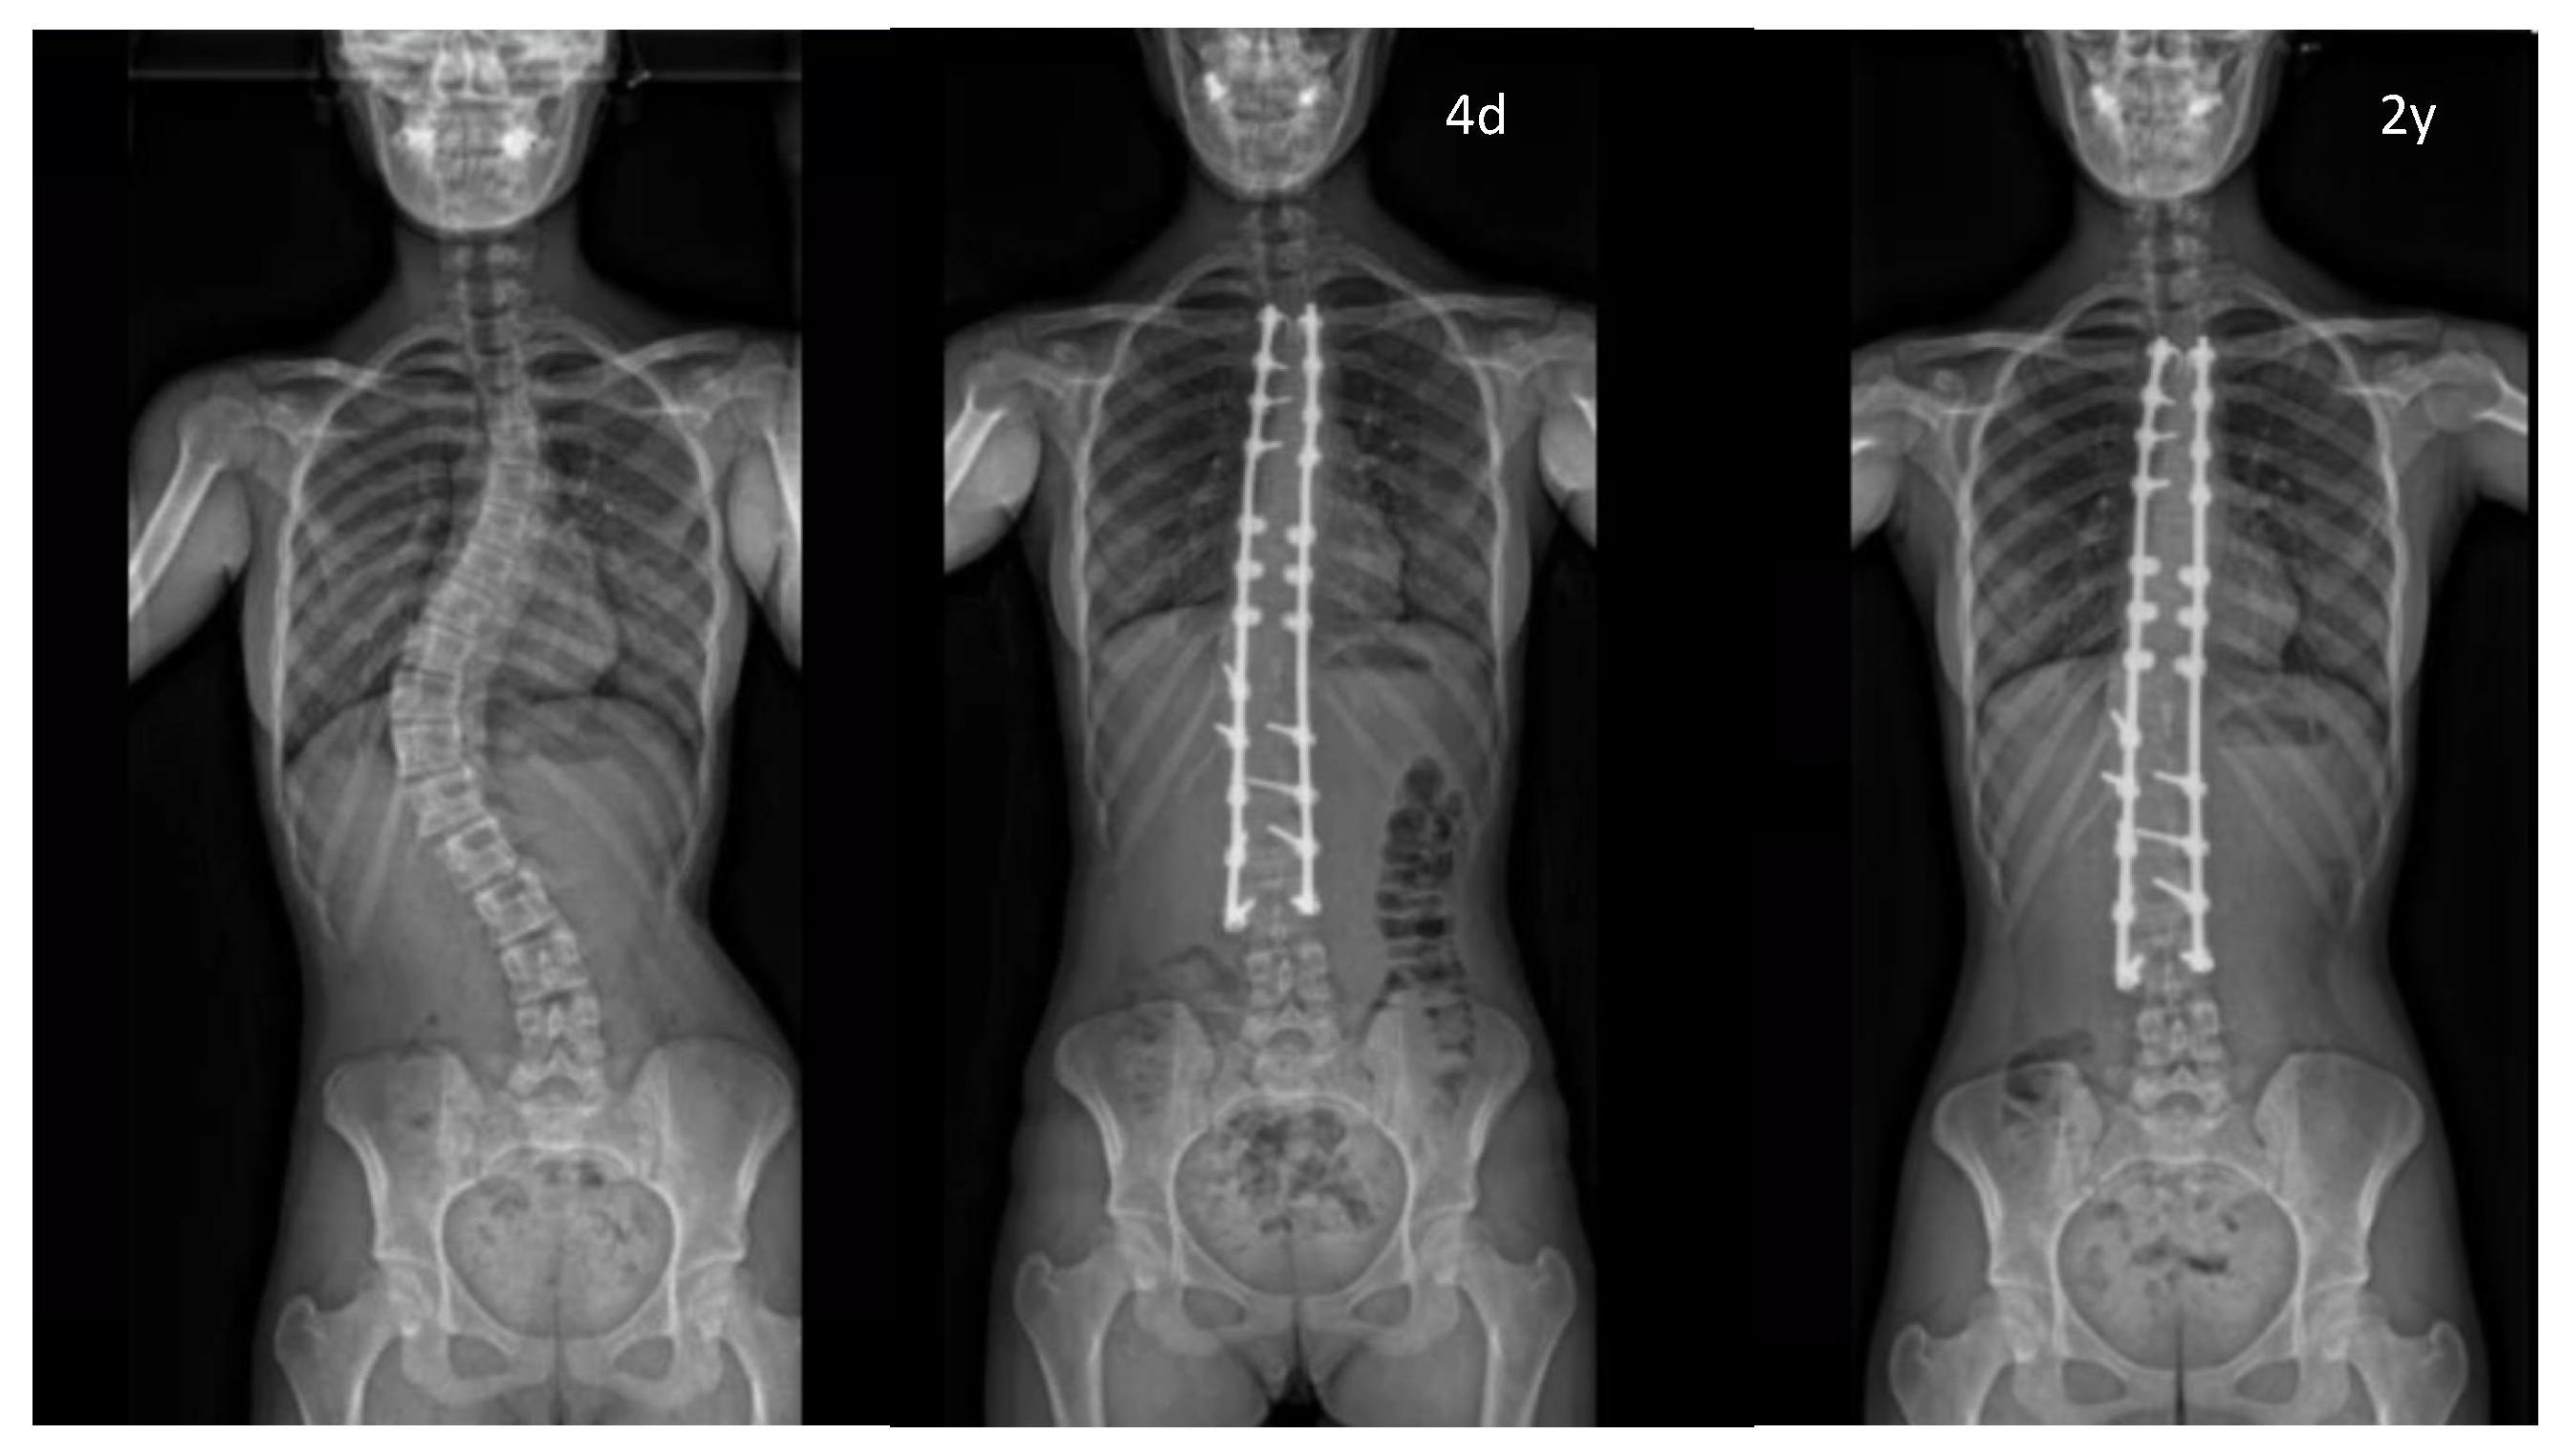

3.4. Radiographic Analysis

| Pre-op | 62.7 ± 22.7 (43) | [30–130] | / | 70.4 ± 24.9 (18) | [42–130] | / | 57.2 ± 19.6 (25) | [30–120] | / |

| 1st erect | 26.5 ± 16.4 (43) | [0–68] | p < 0.05 from pre-op (7.10−13) | 30.1 ± 17.9 (18) | [2–68] | p < 0.05 from pre-op (3.10−6) | 23.9 ± 15.1 (25) | [0–50] | p < 0.05 from pre-op (2.10−8) |

| 3–6 months | 24.0 ± 13.9 (25) | [0–50] | p < 0.05 from pre-op (8.10−11) | 23.0 ± 7.1 (2) | [18–28] | p < 0.05 from pre-op (0.02) | 24.1 ± 14.5 (23) | [0–50] | p < 0.05 from pre-op (3.10−8) |

| 24 months | 27.1 ± 16.1 (42) | [0–70] | p < 0.05 from pre-op (10−12) | 31.2 ± 18.6 (17) | [7–70] | p < 0.05 from pre-op (9.10−6) | 24.1 ± 14.1 (25) | [0–52] | p < 0.05 from pre-op (10−8) |

| Correction rate | |||||||||

| Pre-op vs. 1st erect (°) | 36.2 ± 12.0 (43) | [15–70] | / | 40.3 ± 11.4 (18) | [24–70] | / | 33.2 ± 11.7 (25) | [15–70] | / |

| Loss of correction | |||||||||

| 1st erect vs. 3/6 months (°) | −0.55 ± 3.32 (25) | [−8.0–5.0] | p = 0.874—NS | 0.00 ± 5.7 (2) | [−4.0–4.0] | p = 0.950—NS | −0.60 ± 3.25 (23) | [−8.0–5.0] | p = 0.773—NS |

| 1st erect vs. 24 months (°) | −0.65 ± 3.24 (42) | [−7.0–7.0] | p = 0.671—NS | −1.12 ± 3.52 (17) | [−7.0–7.0] | p = 0.685—NS | −0.18 ± 2.97 (25) | [−6.5–6.0] | p = 0.868—NS |